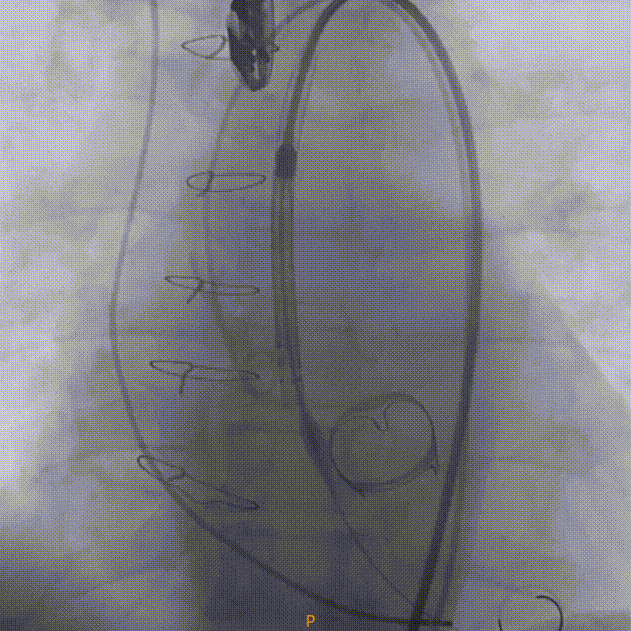

手术过程

在放射科,超声科和麻醉科的通力协作下,顺利完成了术前准备,术者团队在术中谨慎建立轨道,根据主动脉根部造影的结果,初步判断释放体位是否合适观察瓣叶活动度、是否合并反流,选择合适的跨瓣体位。瓣膜释放前优先确认猪尾管位置,避免瓣膜在释放过程中脱载。